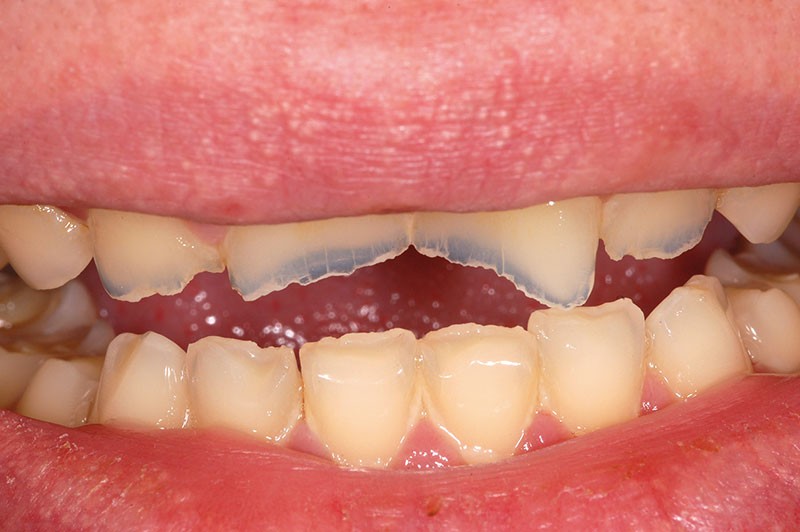

À l’examen clinique, les dents, principalement antérieures, présentent des pertes de substances importantes de classe V selon la classification ACE (Anterior Clinical Erosive Classification) de Vailati [1] (fig. 1 à 6).

Les examens complémentaires, dont un sondage parodontal, montrent l’absence de maladie parodontale (fig. 7).

Le parodonte marginal est de type 1 selon la classification de Maynard et Wilson [2]. On note également la présence d’une grande quantité de gencive attachée située apicalement par rapport aux lésions dentaires.